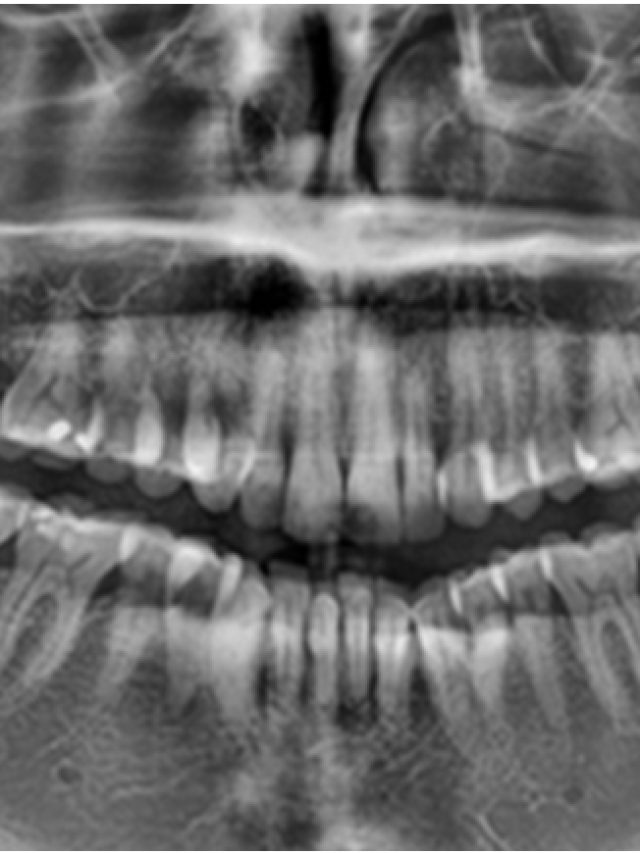

4 Top-notch Solutions for Pericoronitis: What You Need to Know Gustavo Assatourians / February 4, 2023